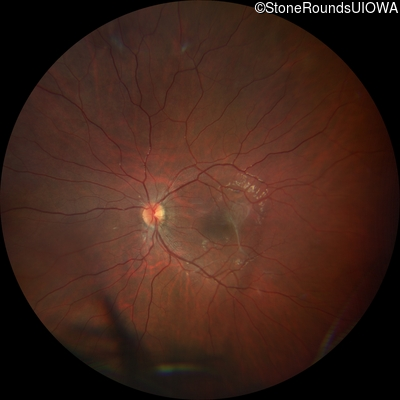

This 9 year old male was noted to have some crossing of his eyes at 2 months of age and the eye exam which followed identified a retinal lesion in the right eye. When he was six years old an epiretinal membrane was noted in his left eye. Two years later it was decided that it was a thin hamartoma in that eye as well. He underwent neuroimaging at age 7 which identified bilateral acoustic neuromas.